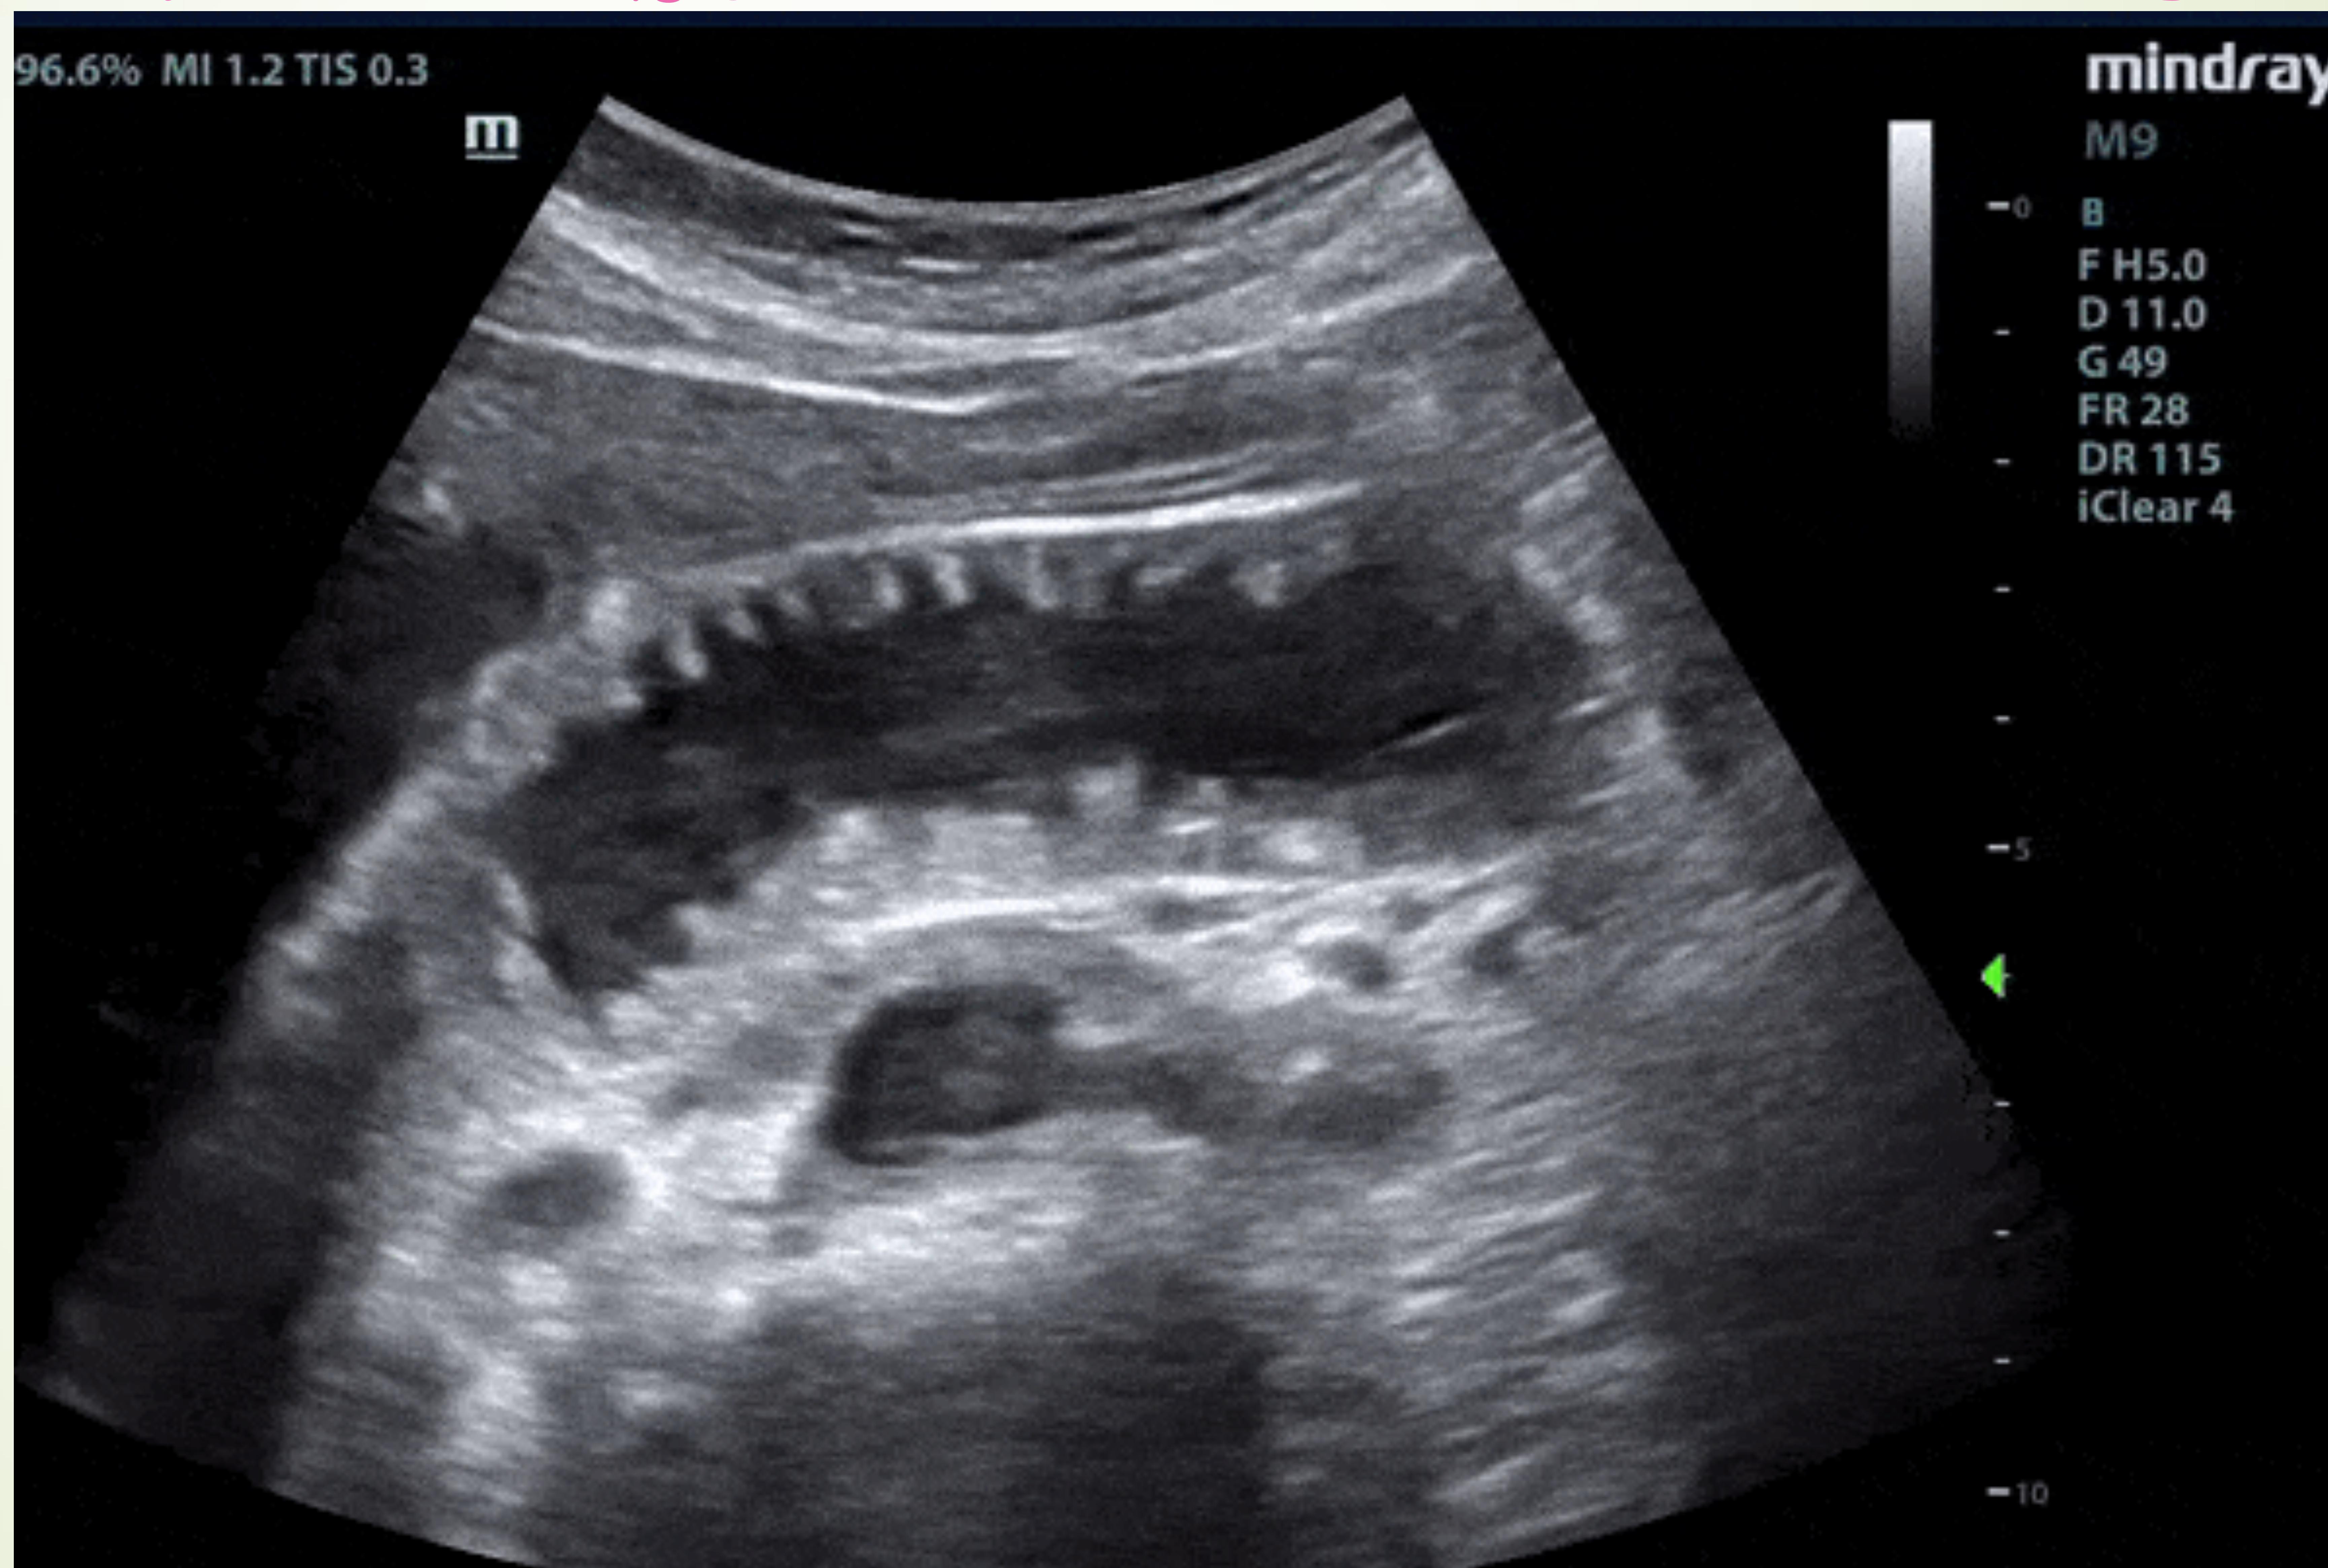

Case #5: Acute Cholecystitis

Presentation: 48yo Obese Female. RUQ pain after eating. Exam: +Murphy’s Sign.

- Gold Standard Image: RUQ Ultrasound (Thickened wall, fluid, stones, sonographic Murphy’s).

- Management: Antibiotics, Cholecystectomy.

Ultrasound showing gallbladder wall thickening and fluid.

Detailed US findings: Wall thickening, Pericholecystic fluid, Gallstones.